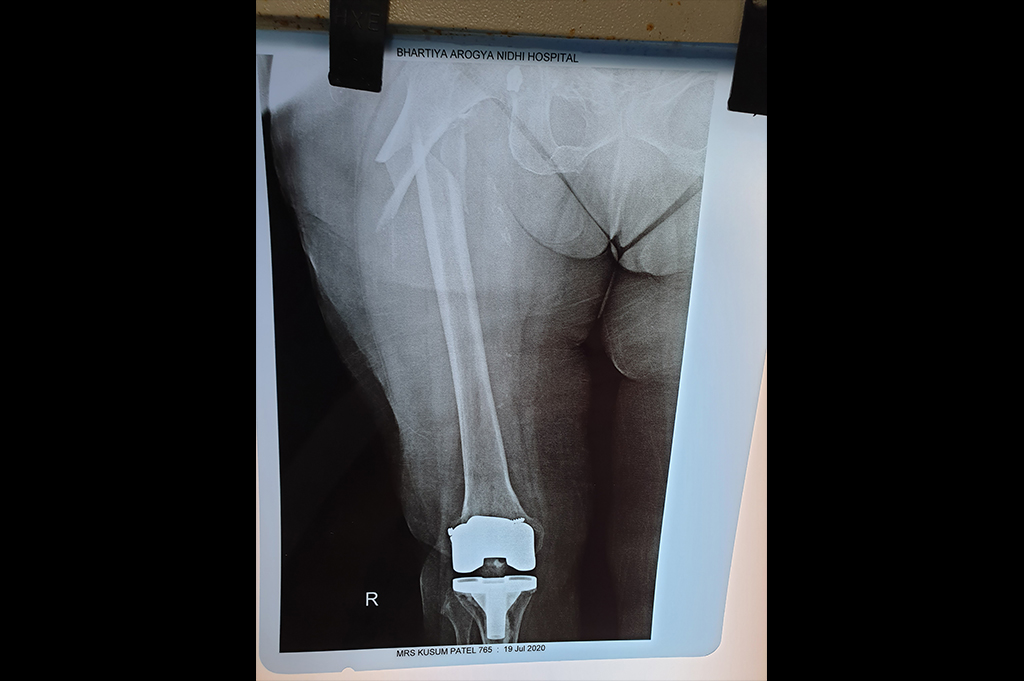

Total Knee Replacement - TKR